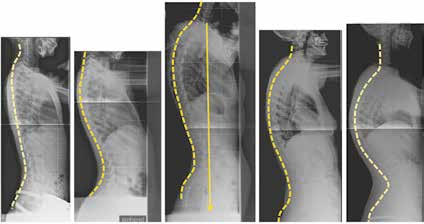

Das dorsale sagittale Wirbelsäulenprofil wird von einer großen Bandbreite an beschwerdefreien Formen geprägt. Ein direkter Zusammenhang zwischen Form und Funktion darf angenommen werden, während die Wahrscheinlichkeit für Beschwerden für den einzelnen Patienten kaum vorhersehbar ist. Werden dagegen Beschwerden diagnostiziert, so kann die Wirbelsäulenstatik in vielen Fällen als gutes Erklärungsmodell herangezogen werden (Abb. 2).

Werden aktuelle Erkenntnisse aus der Wirbelsäulenchirurgie auf die Orthesenversorgung angewendet, so ergeben sich interessante Gesichtspunkte: In der Wirbelsäulenchirurgie steht die sagittale Balance der Wirbelsäule aktuell an oberster Stelle. Dabei werden in die Gesamtbeurteilung der Wirbelsäule das Becken und die Hüften eingeschlossen.

Das neue Konzept „F. B. I.“ (Full Balance Integrated) von J. C. LeHuec bietet nachvollziehbare Lösungsansätze für den Wirbelsäulenchirurgen und liefert damit viele Erkenntnisse, die auch in der Orthesenversorgung so manchen Erfolg oder Misserfolg erklären können 14 (Abb. 5).

Folgende radiologische Parameter werden aktuell verwendet:

- Die Schwerelinie von C7 sollte physiologisch die Deckplatte von S1 schneiden.

- Zum funktionellen Parameter wird der Sacral Slope (SS; Kreuzbeinneigung) = Winkel zwischen einer Deckplattenparallelen S1 mit der Horizontalebene.

- Pelvic Tilt (PT; Beckenkippung) = Winkel zwischen der Lotlinie durch den Femurkopf und der Verbindung zur Sakrumbasis.

- Pelvic Incidence (PI; Tiefe des Beckens) = Winkel zwischen der Verbindungslinie vom Hüftkopfzentrum zur Mitte der Deckplatte S1 und einer Linie, die in einem rechten Winkel zur Deckplatte S1 steht. Dies bildet ein Maß für die Tiefe des Beckens und wird so zum morphologischen Parameter.

- Die Flexion der Hüftgelenke wird durch den Femur Obliquity Angle (FOA; Hüftflexionseinstellung) = Winkel des Femurs zur Vertikalen beschrieben.